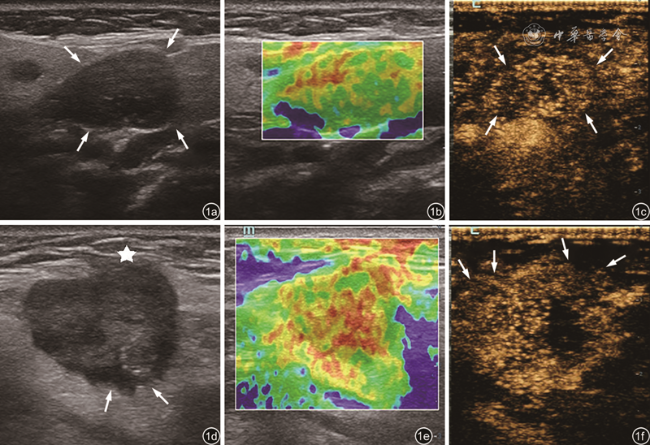

表2 良性与恶性涎腺局灶性病变RTE分级结果比较[例(%)] |

| 组别 | 例数 | Ⅰ级 | Ⅱ级 | Ⅲ级 | Ⅳ级 |

|---|---|---|---|---|---|

| 恶性组 | 43 | 0 | 16(37.2) | 20(46.5) | 7(16.3) |

| 良性组 | 85 | 20(23.5) | 48(56.5) | 14(16.5) | 3(3.5) |

| χ2值 | 27.879 | ||||

| P值 | <0.001 | ||||

注:RTE为实时超声弹性成像 |

表3 良性与恶性涎腺局灶性病变CEUS分型结果比较[例(%)] |

| 组别 | 例数 | Ⅰ型 | Ⅱ型 | Ⅲ型 | ||

|---|---|---|---|---|---|---|

| Ⅱa | Ⅱb | Ⅱc | ||||

| 良性组 | 85 | 17(20.0) | 40(47.1) | 9(10.6) | 10(11.8) | 9(10.6) |

| 恶性组 | 43 | 2(4.7) | 6(14.0) | 3(7.0) | 31(72.1) | 1(2.3) |

| χ2值 | 9.086 | |||||

| P值 | 0.011 | |||||

注:CEUS为超声造影 |